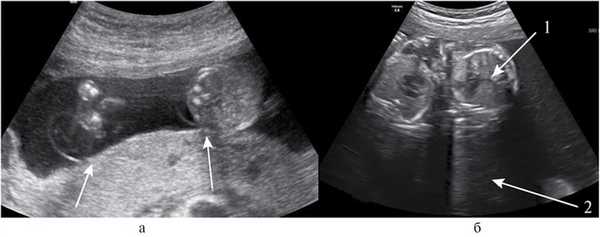

В сроке беременности 20 нед пациентка направлена для медико-генетического консультирования (МГК) в связи с возрастом 35 лет и трехплодной беременностью. При проведении ультразвукового (УЗ) осмотра врачом, имеющим большой опыт в работе с многоплодной беременностью, высказано предположение о том, что тройня является МХТА. Плацента располагалась по задней стенке матки, межамниотические мембраны тонкие, толщиной 0,9 и 1,3 мм, отходят они под прямым углом от поверхности плаценты (Т-признаки) (рис. 2, а) [12]. Все плоды оказались женского пола.

Рис. 2. УЗ-изображения МХТА тройни в 22—23 нед гестации. а — единственная плацента, расположенная по задней стенке матки. Стрелками обозначены Т-признаки; б — поперечные срезы грудной клетки на уровне сердца двух плодов-доноров (стрелка 1); выраженное многоводие у плода реципиента (стрелка 2).

При УЗИ в 22 нед беременности установлено: МХТА тройня, ФФТС II степени, многоводие у первого плода, маловодие у второго и третьего плодов (см. рис. 2, б). Результаты фетометрии представлены в таблице.